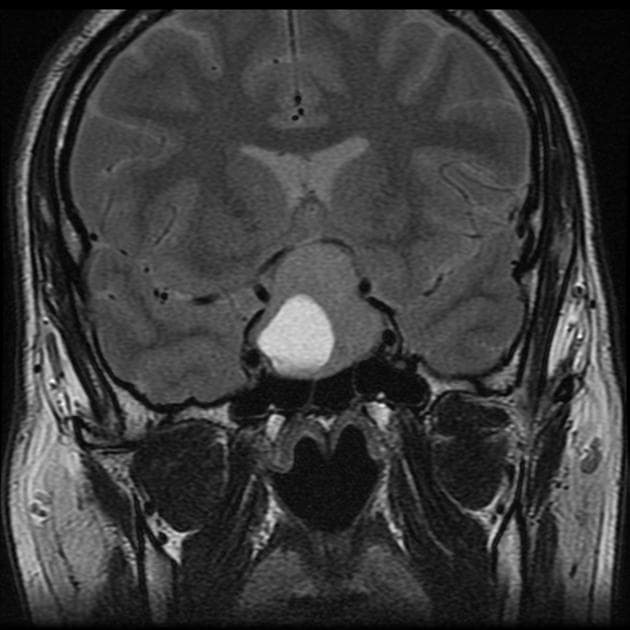

Coronal T1

MRI•Coronal T1•1 Img

- Tuyến yên (pituitary gland) giãn tròn, lệch về bên phải đường giữa, đẩy cuống tuyến yên sang trái.

- Trên hình ảnh sau tiêm thuốc cản quang, u tuyến yên nhỏ (pituitary microadenoma) tăng quang kém hơn so với mô tuyến yên xung quanh.

Chụp cộng hưởng từ (MRI) cho thấy các hình ảnh phù hợp với u tuyến yên nhỏ (pituitary microadenoma).

U tuyến yên nhỏ (pituitary microadenoma)

U tuyến yên nhỏ là các khối u lành tính xuất phát từ thùy trước tuyến yên, có kích thước nhỏ hơn 10 mm. Chúng thường được phát hiện tình cờ hoặc khi có các rối loạn nội tiết như tăng prolactin, bệnh Cushing hoặc to đầu chi. Trên cộng hưởng từ (MRI), đặc biệt là hình ảnh T1 sau tiêm thuốc cản quang, u tuyến yên nhỏ thường hiện diện như các tổn thương tăng quang kém trong nhu mô tuyến yên, với tốc độ tăng quang chậm hơn mô tuyến yên bình thường xung quanh. Mô tuyến yên bình thường tăng quang nhanh nhờ hệ tuần hoàn cửa, trong khi u tuyến tăng quang chậm hơn. Chẩn đoán chính xác đòi hỏi hình ảnh độ phân giải cao và đối chiếu với lâm sàng cùng các xét nghiệm nội tiết. Hầu hết u tuyến yên nhỏ ổn định theo thời gian, nhưng một số có thể phát triển hoặc gây rối loạn hormone tiến triển, cần theo dõi hoặc điều trị.